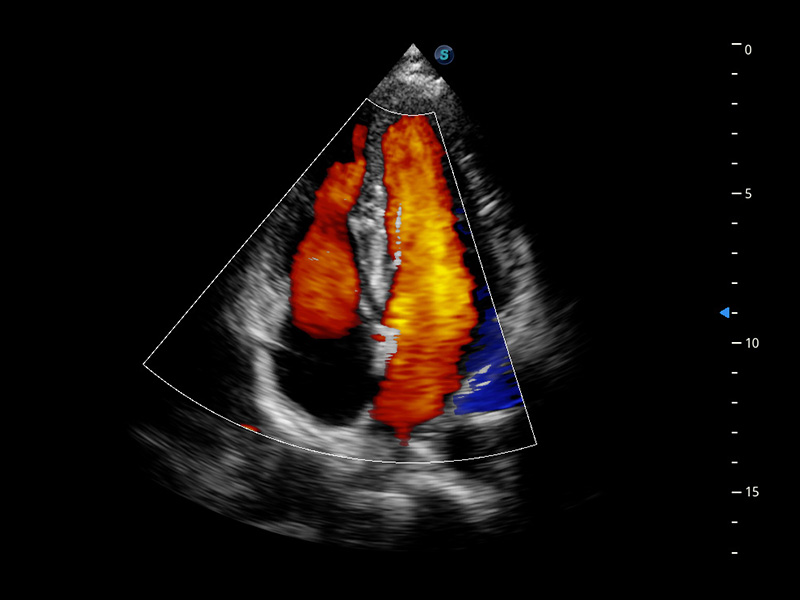

Cardiovascolare avanzato

Si impegna a fornire una soluzione completa per la valutazione cardiaca

Dotato dell'esclusivo trasduttore a cristallo singolo SonoScape e di una tecnologia di elaborazione all'avanguardia, P60 si impegna a ripristinare ogni dettaglio ed elemento per una diagnosi precisa. La nuova analisi quantitativa del miocardio (MQA) fornisce un referto quantitativo approfondito sulle dinamiche del movimento della parete miocardica globale e regionale del ventricolo sinistro, offrendo ai medici una valutazione completa delle funzioni miocardiche.

• Stress Echo

• MQA con analisi della deformazione

• TDI (Tissue Doppler Imaging)

• Opacizzazione VS

• Auto EF